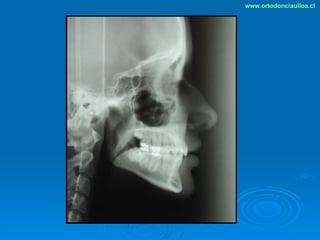

Este documento presenta dos casos clínicos de pacientes que recibieron tratamiento de ortodoncia. El primer caso fue de una paciente femenina de 14 años con apiñamiento dental y mordida cruzada que fue tratada mediante extracción de premolares y alineamiento dental. El segundo caso fue de un paciente masculino de 14 años con clase II esqueletal y desarmonía dentomaxilar que fue tratado con extracción de premolares y corrección de mordida. Ambos casos mostraron mejoría después de 3 años de tratamiento.